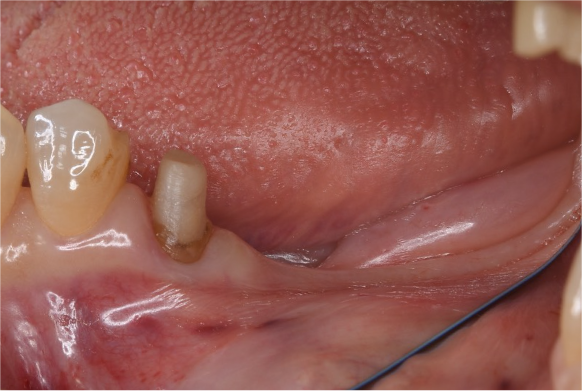

症例3

| 通院期間 | 9か月 |

| 来院回数 | 12回 |

| 治療費 | 総額:835,000円(税抜) 【内訳】 インプラント埋入手術250,000円、GBR(骨再生手術)150,000円、2次手術+FGG(遊離歯肉移植術)55,000+60,000円、仮歯30,000円、インプラント上部構造(セラミッククラウン)170,000円、隣在歯セラミッククラウンのやりかえ120,000円 |

| リスクと副作用 | 定期的なメンテナンスが必要、術後若干の腫れと痛み |

| ここがこだわりのポイント!☝ | インプラント周囲に角化歯肉と言われる健常な歯肉がなかったので、口蓋からの歯肉移植を行っています💡この角化歯肉がないと、インプラントをしてもうまく歯磨きができないことがあります。 |